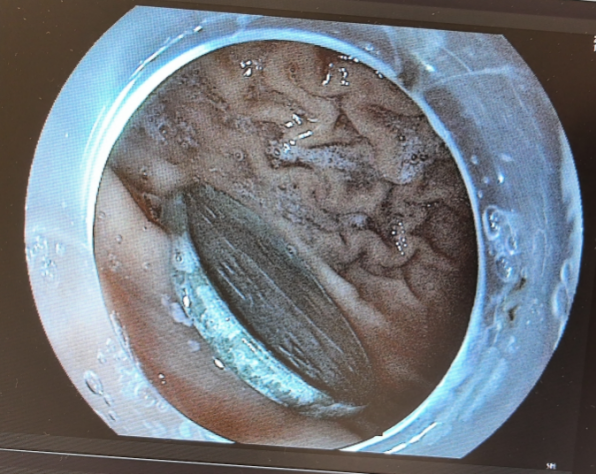

专家妙手取“金” 硬币取出时已被腐蚀发黑了

这次腹部立位片检查的结果显示,硬币在孩子的胃里一动没动。接诊的儿科副主任医师王艳丽担心胃酸的腐蚀会对胃粘膜造成刺激,金属异物在胃里呆的时间过长会导致胃粘膜水肿,有些异物甚至会引起胃部糜烂或者溃疡,于是建议让孩子在全麻下进行胃镜下异物取出术。

不到3分钟,王艳丽就将卡在强强胃里的硬币取了出来,整个手术过程迅速而精准。被取出来的一毛钱的硬币,直径约有1.9厘米宽,王艳丽表示,吞进异物有些对人体是有害的,特别像这种金属类的异物或者一些对消化道有潜在危害的异物,如果观察超过72小时未排除,还是建议应及时取出。术后,强强精神状态挺好,没有什么不良反应和副损伤,也能正常进食。